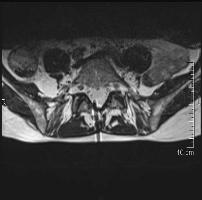

Durch den Einsatz unserer modernen Magnetresonanztomographen, der Firma Siemens (1,5 Tesla starkes Magnetom Essenza ®) bei den Therapien, kann eine präzise, strahlungsfreie und gewebeschonende Behandlung ohne Komplikationen wie Gefäß- und Nervenverletzung erfolgen.

Die Behandlung wird unter exakter kernspintomographischer (MRT) Kontrolle durchgeführt. Der Patient liegt bequem auf der Untersuchungsliege, ähnlich wie bei CT-Gestützten Interventionen. Vor der eigentlichen Punktion des zu behandelnden Areals ist es aber noch die genaue Lokalisation festzulegen. Um die Punktionsstelle exakt zu erfassen, wird dem Patienten vorab eine Markierung auf die Haut geklebt, die später als Messinstrument dienen soll. Zusätzlich bekommt der Patient von uns eine flexibeler Spule (Messinstrument) über den Rücken geschnallt um die Atemverschiebung zu minimieren. Nun wird durch eine sagitale MRT Aufnahme (TRUFI multi localizer) wird zuerst die Lage der eigentlichen Schmerzquelle genauestens lokalisiert. Danach folgen, ähnlich wie bei der CT transversale  Schichtaufnahmen (T1w oder T2w-TSE, 3mm, mit geringer Matrix, max 192 und hoher Bandbreite 200+, welche die Aquisitionszeiten extrem gering halten < 20 s). Nachdem die Punktionsstelle auf die Haut eingezeichnet worden ist wird eine gründliche Hautdesinfektion und örtlicher Betäubung eine hauchdünne Nadel (aus antimagnetischen Material) unmittelbar in die Nähe der gereizten Nervenwurzel oder der Facette gebracht. Dann erfolgt eine Kontrolle der Nadellage unter der Gabe eines MR-Kontrastmittels. Erst bei absolut korrekter Lage der Injektionsnadel werden die Medikamente gespritzt.